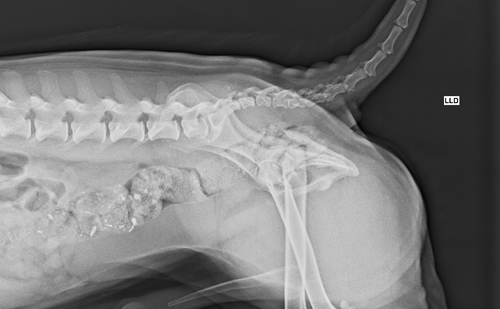

Oi, me chamo Bárbara e estou fazendo essa vaquinha online com um propósito muito especial: ajudar um cachorro de rua, chamado de Nonô, que foi vítima de um atropelamento. Ele acabou sofrendo fraturas graves em uma de suas perninhas.

Nosso objetivo com esta vaquinha online é arrecadar 2.220,00 reais para cobrir os gastos da cirurgia que irá reparar as fraturas na perninha do Nonô. Esse procedimento é crucial para aliviar sua dor, permitir sua locomoção e garantir sua qualidade de vida. Com a sua ajuda, podemos dar ao Nonô uma nova chance de correr, brincar e o melhor: encontrar um lar amoroso.